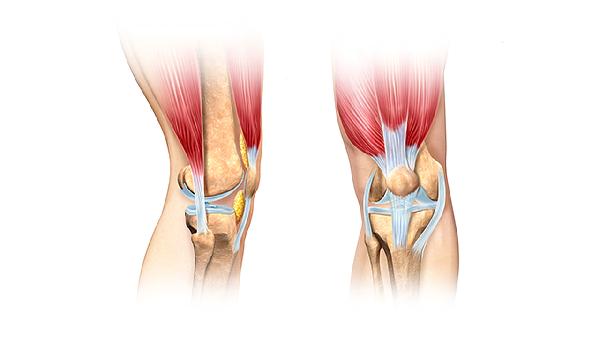

日常補充建議搭配維生素C促進膠原合成,運動后補充效果更佳。膝關節不適者可配合低沖擊運動如游泳,避免爬山等負重鍛煉。飲食中可增加銀耳、桃膠等植物膠質食物,控制咖啡因攝入以免影響鈣吸收。定期骨密度檢測能客觀評估補充效果,中重度骨質疏松患者需在醫生指導下聯合藥物治療。